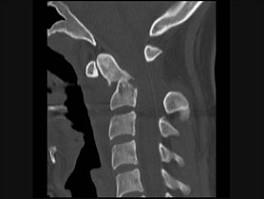

问题 本病例有颈部外伤,主诉颈部疼痛,活动受限,请结合所提供CT图像,选出最佳选项 ( )

选项 A、寰枢关节脱位 B、未见异常 C、C前弓骨折 D、C后弓骨折 E、C齿状突骨折

答案 E